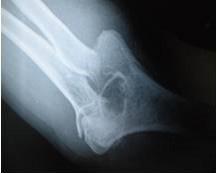

Manejo ortopédico de la artropatía hemofílica en México. Por: Dr. Armando R. Hernández Salgado, Ortopedista y Traumatólogo, Cirujano de Artroscopia y Cirugía de Rodilla, Especialista en Artropatía Hemofílica, Asesor Voluntario de FHRM. Pág. 109

Tratamiento oportuno evita lesiones incapacitantes y reduce riesgo de fallecimiento por Hemofilia. Por Redacción. Pág. 117

Embolización de la arteria genicular media para el tratamiento definitivo de los sangrados en las rodillas de pacientes hemofílicos. Por: Dr. Guillermo Capetillo Morales, Médico Traumatólogo Ortopedista. Pág. 118